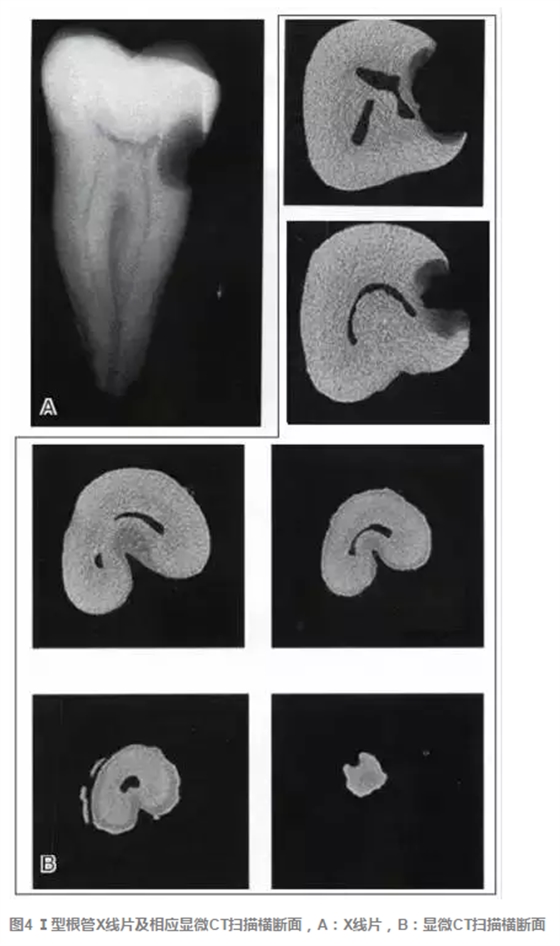

傳統(tǒng)的Melton C形根管分類法雖深化了對根管結(jié)構(gòu)的認識,但由于是基于組織學的分類,不能指導臨床實踐。有學者基于C形根管X 線特征,結(jié)合顯微CT掃描結(jié)果,提出了一種新的分類方法,便于臨床應(yīng)用。這種分類方法將下頜第二磨牙分為3型:①Ⅰ型:融合型,X線片上見2個根管,但在根尖區(qū)融合;②Ⅱ型:分離型,X線片上見2個根管且相互獨立;③ Ⅲ型:不對稱型,X線片上雖有2個根管相互獨立,但一長一短,互不對稱(圖3)。各類型C形根管X線特征、顯微CT掃描及重建結(jié)果見圖4~9。